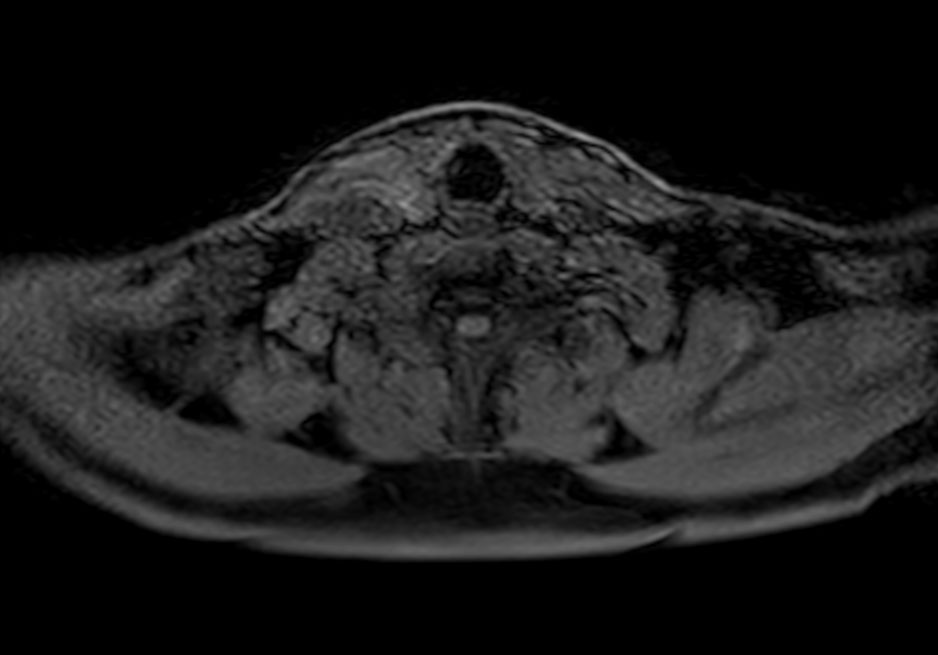

Axial T1w TSE